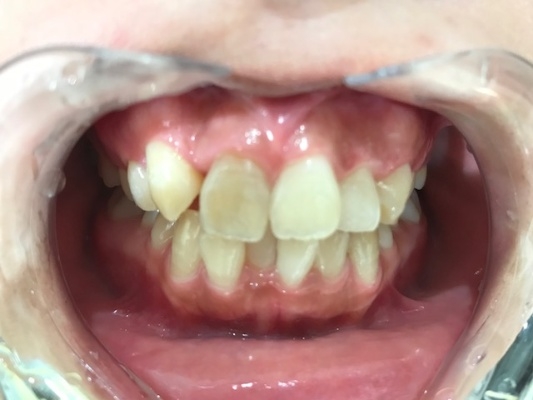

術前口腔内写真 正面観

○前歯の前突した歯を治したい

○八の字型の歯並びを改善したい

○笑った時の歯のアーチを綺麗にしたい